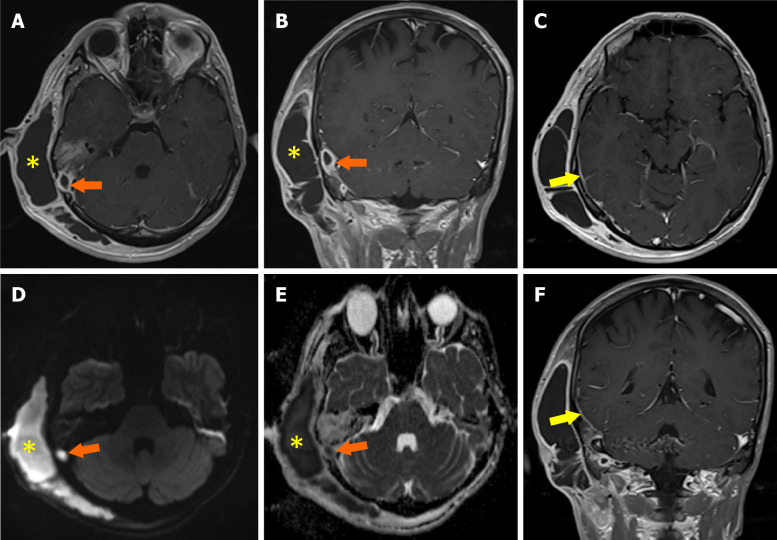

慢性中耳炎(COM)是一种影响中耳和乳突腔的长期炎症,通常导致进行性结构损伤和功能缺陷。放射成像是诊断疾病、评估其严重程度和识别可能的并发症的基础。文献显示颅外、颅内合并症患病率为0.69% ~ 5%,颅内合并症死亡率为26%。虽然磁共振成像在区分软组织异常和检测颅内延伸(如脑膜炎、脑脓肿和乙状窦血栓形成)方面特别有用,但高分辨率计算机断层扫描仍然是评估骨侵蚀、胆脂瘤和乳突受累的首选方式。关键并发症,如听骨链破坏、面神经损伤和迷路瘘管可以通过先进的成像方式精确识别,允许及时有效的手术干预。这篇小型综述强调了放射学在诊断和治疗COM中的重要作用,强调了有助于早期发现和指导治疗决策的关键影像学发现。放射科医生、耳鼻喉科医生和传染病专家之间的合作方法对于改善受影响患者的临床结果至关重要。

Chronic otitis media (COM) is a long-standing inflammatory condition affecting the middle ear and mastoid cavity, often resulting in progressive structural damage and functional deficits. Radiological imaging is fundamental in diagnosing the disease, assessing its severity, and identifying possible complications. The literature indicates that the prevalence rates of extracranial and intracranial complications range from 0.69% to 5%, while the mortality rate for intracranial complications is 26%. While magnetic resonance imaging is particularly useful in distinguishing soft tissue abnormalities and detecting intracranial extensions like meningitis, brain abscess, and sigmoid sinus thrombosis, high-resolution computed tomography remains the preferred modality for evaluating bony erosion, cholesteatoma, and mastoid involvement. Key complications such as ossicular chain destruction, facial nerve damage, and labyrinthine fistulae can be precisely identified using advanced imaging modalities, allowing for timely and effective surgical intervention. This minireview underscores the essential role of radiology in both diagnosing and managing COM, highlighting critical imaging findings that facilitate early detection and inform treatment decisions. A collaborative approach among radiologists, otolaryngologists, and infectious disease specialists is crucial for improving clinical outcomes in affected patients.